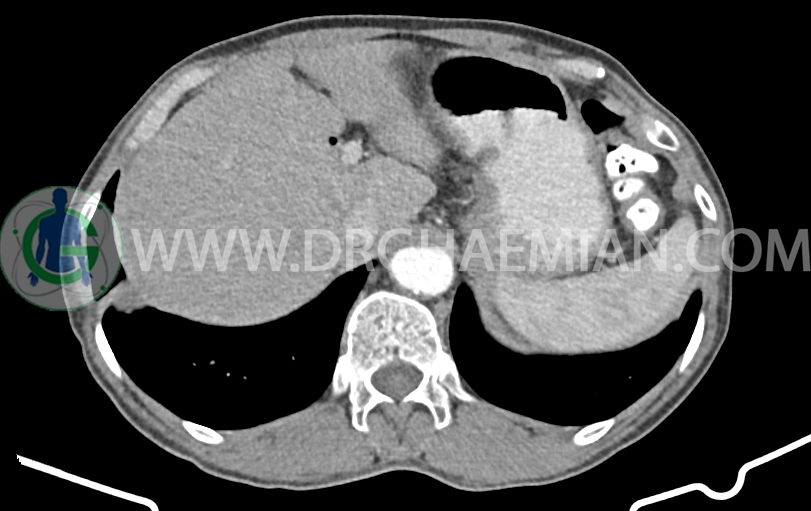

توده با حدود اسپیکوله به ابعاد mm 51x33x24 حاوی چند کانون کلسیفیه کوچک در قاعده ریه راست مجاور دیافراگم مشهود است که مطرح کننده ضایعه نئوپلازیک مثل توده اولیه و متاستاز می باشد. (نیازمند بررسی بافتی – یافته جدید نسبت به سی تی اسکن 1401/06/06 (

کانون کلسیفیه کوچک فاقد اهمیت بالینی در لوب راست کبد رویت شد

پنوموبینی در لوب چپ کبد مشهود است.

افزایش ضخامت ناحیه کاردیا مشاهده می شود )تطبیق با اندوسکوپی)